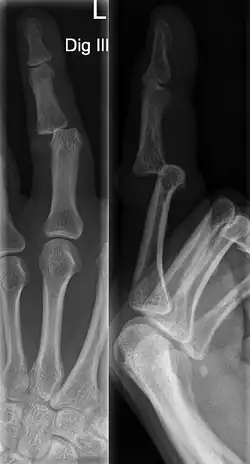

A jammed finger can generally be diagnosed by a physical examination. Bone or joint deformity may indicate potential dislocations or fractures.[6] The basic structure of the finger includes three bones with joints in between each.[9] The joint closest to the tip is the distal interphalangeal (DIP) joint. The next joint, moving closer to the hand, is the proximal interphalangeal (PIP) joint. The thumb differs by only having two bones and one interphalangeal joint.[10]

The injured finger may be examined to determine where the pain is worst.[3] If the finger is sprained or dislocated, pain will be worse at the joint rather than the bone.[3] Due to the risk of dislocations or fractures, X-rays should be conducted prior to testing joint stability. This allows for prior detection of a dislocation or fracture.[3] It is recommended that a variety of views (lateral, oblique, and anteroposterior) are observed.[3] In extremely painful cases, a digital nerve block may be done to better assess the finger. This is where anesthetic is injected to either side of the base of the affected finger to reduce pain.[3]

DIP dislocations are much less common than PIP dislocations.[3] This is thought to be due to the increased stability of the DIP joint,[15] though not for certain.[2] Dislocations can be categorized based on the direction that the fingertip moves in relation to the knuckle.[6] If in the direction of the palm, it is a volar dislocation. If in the direction of the back of the hand, it is a dorsal dislocation.[6] If in the direction to either side, it is a lateral dislocation.[2] Of the three, dorsal dislocations are most common.[6] Dorsal dislocations of the PIP commonly lead to volar plate damage.[2]

Dislocations are often visually obvious due to joint deformity.[2] Therefore, x-rays may or may not be utilized in the diagnosis of a suspected dislocation. Though, they can provide feedback on post-reduction status if attempted prior to formal medical evaluation.[2] Dislocations may also be complicated by a tandem fracture.[5] These cases may necessitate a visit to a hand surgeon for surgery.[2]

Fractures are instances where the bone's structural integrity has been compromised.[20] If a jammed finger produces a fracture, pain will be greatest at the bone as opposed to the joint.[2] There may also be visual deformation of the bone itself.[6] As with any skeletal injury, an x-ray can be conducted to verify the presence of a fracture.[1] The distal phalanx is especially vulnerable to avulsion fractures.[1] These avulsion fractures are common following a first time dislocation of the DIP.[1]